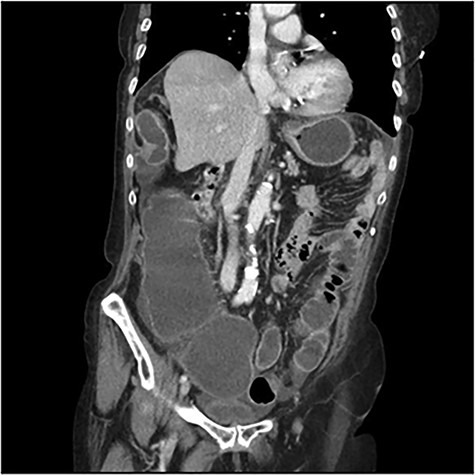

The scanner demonstrated a colonic occlusion resulting from an incarceration, which was diagnosed as a hernia of Bochdalek containing the hepatic angle of the colon (Fig. 2–4).

: CT scan images demonstrating a right diaphragmatic hernia containing intestine.

At the relecture of the images, they showed two old rib fractures. When asked to the patient, she mentioned a past history of a fall 2 years earlier, which directed us to the diagnostic of delayed right diaphragmatic rupture.